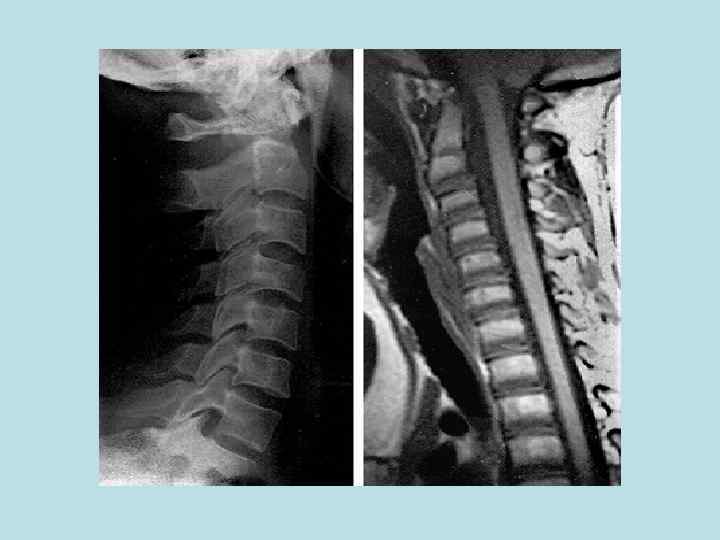

Объект и методы исследования в анатомии • Неживые объекты • Живые объекты - - - Вскрытие трупов и препарирование Бальзамирование Распилы частей тела и органов Метод инъекции и коррозии Изготовление сухих препаратов по В. Л. Груберу и Б. А. Шору и др. Просветление тканей органов Метод бьющей капли Макро - микроскопия Пластинация органов и трупов Гистотопография Световая и электронная микроскопия Соматоскопия Антропометрия Рентгеноанатомия (рентгенография, томография, электрорентгенография) - Эхолокация Компьютерная томография Магнитно-резонансная томография Эндоскопия Эксперименты на животных Математические и статистические методы